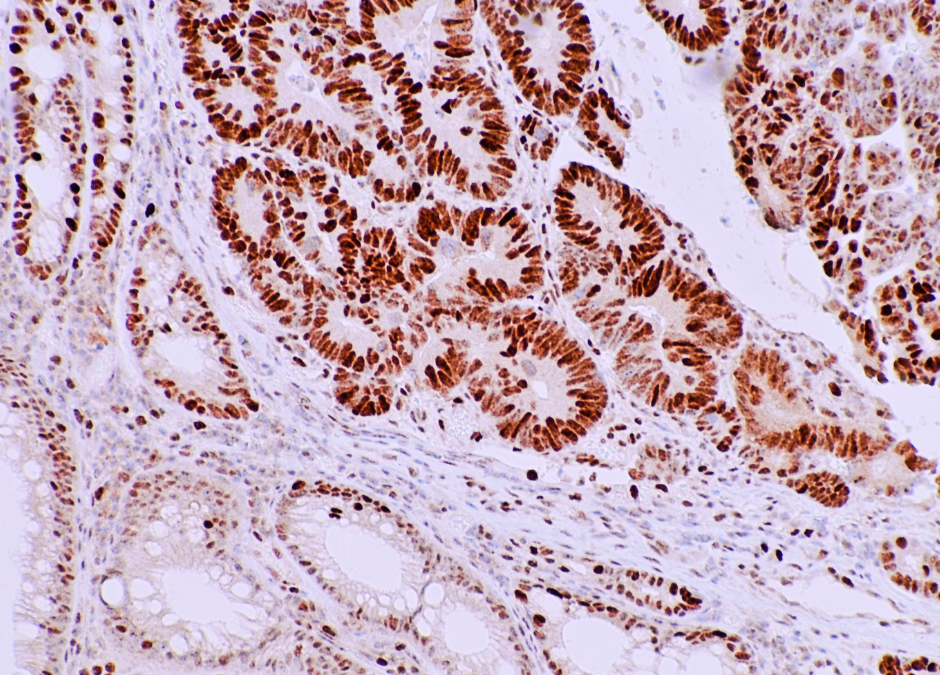

March 29, 2022March Health Awareness Featured Topic: 2022 Update on Colorectal Cancer Screening and Surveillance Recommendations

While colorectal cancer (CRC) is preventable, it remains a major U.S. public health issue, as it is the third most prevalent and deadly malignancy. New screening guidelines recommend that all Americans at average risk for CRC undergo screening starting at age 45, lowered from age 50. It is estimated that one-third of Americans are not up-to-date with screening. As of 2019, only 67% of eligible individuals had been tested. The U.S. Multi-Society Task Force on CRC released updated recommendations in 2020 on surveillance intervals after colonoscopy and polypectomy. It is imperative to make substantive progress in CRC screening because lives are at stake if we cannot enhance testing uptake.